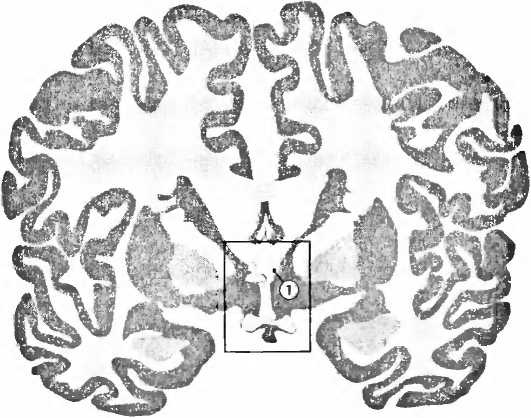

Все данные указывают на то, что гендерные проблемы возникают уже во время пребывания в матке. Были найдены небольшие изменения в генах, причастных к воздействию гормонов на развитие мозга, которые повышают вероятность транссексуальности. Ненормальный уровень гормонов плода или медикаменты, которые женщина принимает во время беременности и которые препятствуют расщеплению половых гормонов, могут увеличивать вероятность транссексуальности. Сексуальная дифференциация половых органов происходит в первые месяцы беременности, а сексуальная дифференциация мозга — на второй стадии. Поскольку оба эти процесса происходят в разные периоды времени, существует теория, что при транссексуальности они протекают независимо друг от друга и подвергаются различным влияниям. Если это так, то у М—>Ж транссексуалов следовало ожидать наличия фемининных структур в маскулинном мозге, а у Ж—>М гранссексуалов — наоборот. В 1995 году мы действительно обнаружили такую инверсию полового различия в одной небольшой структуре в мозге посмертных доноров. Результаты нашей работы были опубликованы в журнале Nucure. Речь шла об опорном ядре концевой полоски (bed nucleus of stria terminalis, BST) в гипоталамусе, маленькой структуре, причастной к многим аспектам нашего сексуального поведения (рис. 9, 10). Центральная часть этого ядра (BSTc) у мужчин вдвое больше и содержит вдвое больше нейронов, чем это наблюдается у женщин. У М—>Ж транссексуалов мы обнаруживаем женскую BSTc. Единственный мозг одного Ж—>М транссексуала, который мы могли изучать, — материал, всё еще более редкий, чем мозг М—>Ж транссексуалов, — имел действительно мужскую BSTc. Так что мы могли исключить то, чао инверсия половой дифференциации мозга транссексуалов была вызвана изменением уровня гормонов во взрослом состоянии. Инверсия, таким образом, должна была иметь место в период развития мозга. Если вы опубликуете нечто действительно интересное, то самое любезное, что вы услышите от большинства ваших коллег, это: «Прежде всего результаты должны быть подтверждены независимой группой исследователей». Процесс может затянуться надолго. Мне потребовалось двадцать лет, чтобы собрать эти материалы о мозге. Поэтому я очень обрадовался, когда в прошлом году группа Иванки Савич из Стокгольма опубликовала исследование с функциональной томографией мозга живых транссексуалов. Они еще не подвергались операции и не принимали гормонов. Им давали в качестве раздражителя мужские и женские феромоны, летуучие вещества, запаха которых мы на сознательном уровне не ощущаем. ![]() ![]() Рис. 9. В базальном отделе боковых желудочков (ventriculi laterales), выше ростральнее и медиальное миндалевидного тела, лежит (1) опорное ядро концевой полоски (bed nucleus of stria terminalis, BST), маленькая область мозга, существенная для сексуального поведения. ![]() Рис. 10. Центральная часть опорного ядра концевой полоски (bed nucleus of stria terminalis, BSTc, локализацию см. на рис. 9) у мужчин (А, С) в два раза больше и содержит в два раза больше нейронов, чем у женщин (В). У М—>Ж транссексуалов мы находим BSTc женского типа (D). Единственный Ж—>М транссексуал, которого мы могли изучить (еще более редкий материал, чем мозг М—>Ж транссексуалов), действительно имел маскулинную BSTc. Это изменение полового различия у транссексуалов согласуется с их гендерной идентичностью (ощущением себя мужчиной или женщиной), а не с хромосомным полом или полом, указанным в их документах. LV — латеральный желудочек, BSTm — медиальная часть области BST (J.-N. Zhou et al., Nature, 378: 68–70,1995). Феромоны вызывали различные картины функциональной активации в гипоталамусе и других участках мозга в контрольных группах мужчин и женщин. Характер функциональной активности М—>Ж транссексуалов занимал промежуточное положение по сравнению с изменениями функциональной активности мозга у мужчин и женщин. В прошлом году Вилейанур С. Рамачандран предложил интересную гипотезу в совокупности с предварительными результатами исследований транссексуальности. Его идея заключается в том, что у М—>Ж транссексуалов в коре больших полушарий отсутствует репрезентация пениса, а у Ж—>М транссексуалов в процессе развития не был заложено в коре ареал женской груди. Поэтому транссексуалы не воспринимали эти органы как собственные и хотели от них избавиться. Таким образом, всё указывает на то, что сексуальная дифференциация мозга в ранней фазе развития транссексуалов протекала атипично и что они вовсе не простые психотики, как недавно позволил себе утверждать один психиатр из Лимбурга. С другой стороны, перед тем как браться за лечение, следует с уверенностью исключить желание изменить пол как составную часть психоза, что в некоторых случаях наблюдается при шизофрении, биполярной депрессии и тяжелых расстройствах личности. IV.7 Педофилия